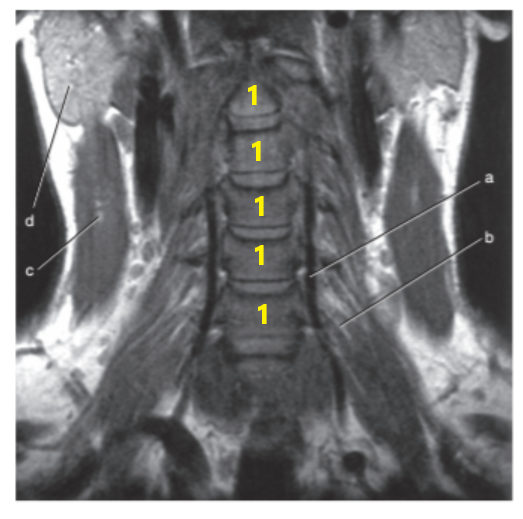

What is # 1's ?

Cervical spine

What is # 4 ?

C-1/C-2

What is # 3 ?

Brain stem